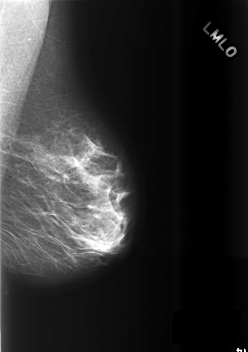

C_0510_1.LEFT_MLO

LEFT_MLO LINES 5632 PIXELS_PER_LINE 3960 BITS_PER_PIXEL 12 RESOLUTION 50 NON_OVERLAY